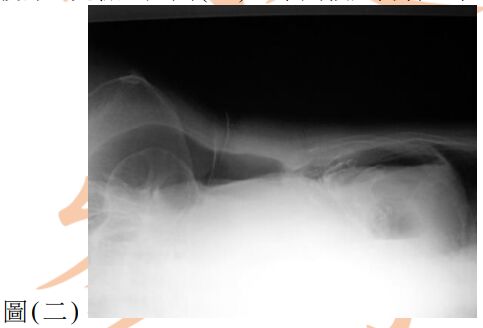

13. 80歲女性為長期糖尿病、高血壓及中風不良於行之病人,因急性腹痛來急診就醫,其平躺之腹部X光如圖(一),另一張左側躺之腹部X光檢查如圖(二),下列敘述何者正確? (A) 推測有腹腔積水,可能為腹腔腫瘤導致 (B) 推測有腹部脹氣,可能為腸阻塞導致 (C) 推測有腹腔積氣,可能為腹腔內中空臟器破裂導致 (D) 為正常腹部影像,只須持續追蹤